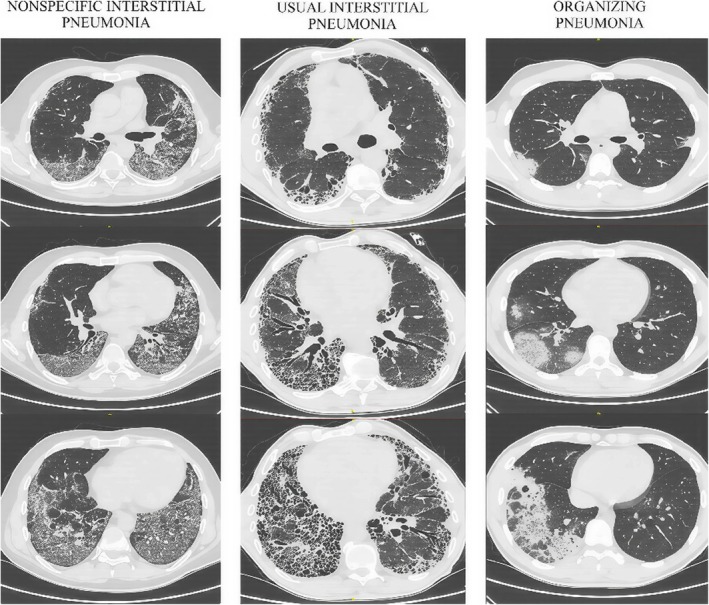

Interstitial lung disease (ILD) associated with connective tissue disease (CTD) is a challenging entity burdened with multiple risk factors and undesirable events. ILD can occur at any time and progress regardless of the underlying disease activity. Apart from the established difficulties in choosing an appropriate treatment strategy for both pulmonary and extrapulmonary involvement, such patients require a holistic and multidisciplinary approach. In an attempt to emphasize the significance of the problem and suggest potential research directions, the authors present four potentially most important and often misdiagnosed complications of the CTD-associated ILD, in the form of acute exacerbation, drug-induced pulmonary toxicity, nonspecific infection, and tuberculosis. Similar clinical manifestations of the patient's progressive deterioration, as well as the complex etiology of pulmonary involvement, raise controversies and force difficult therapeutic decisions. High morbidity and mortality among patients with progressive CTD-associated ILDs necessitate further research in an attempt to enhance the treatment management in each CTD and improve the patients' quality of life.